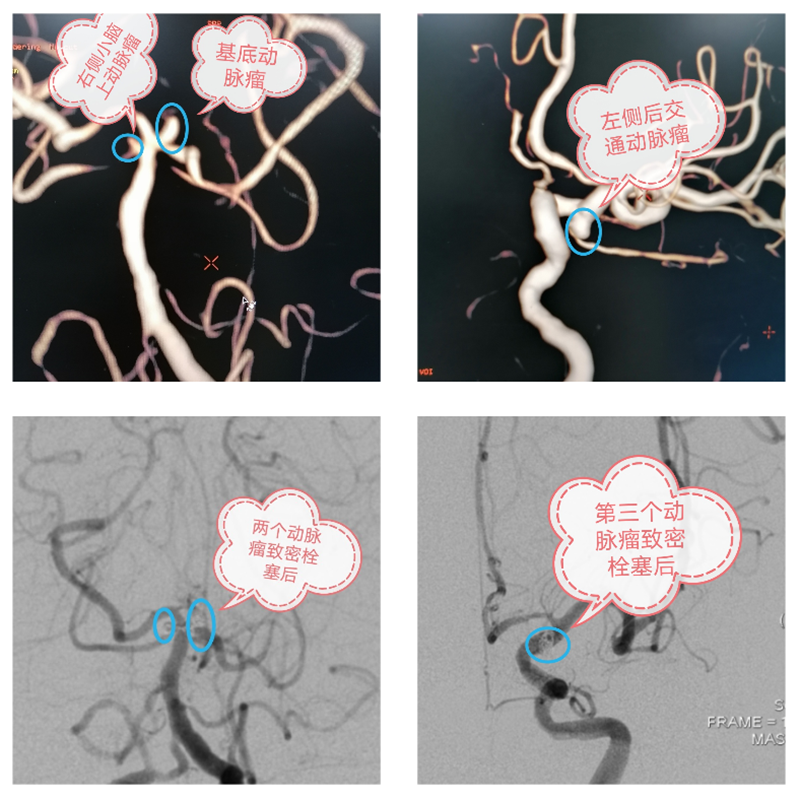

征得家属同意后,手术很快开始。术中,卒中中心手术团队在刘姨基底动脉顶端、右侧小脑上动脉起始段和左侧颈内动脉后交通段各发现一个动脉瘤,经综合考虑手术效果和患者舒适度等方面,手术团队决定对三个动脉瘤全部进行栓塞。该决定也得到家属同意。3个半小时后,手术顺利完成,刘姨生命体征平稳,但还处于昏迷中,被送入神经外科病房接受后续治疗。

“一次栓塞三个动脉瘤,也创下了我们单次手术栓塞动脉瘤最多纪录。”主刀医师、神经外科副主任元少鹏表示,手术的顺利并没有让他们放松警惕,接下来的后续治疗也非常关键。因出血量大导致术后依旧昏迷的刘姨还患有高血压,且一直无规律服药,血压控制不理想,刘姨很可能出现一系列并发症。